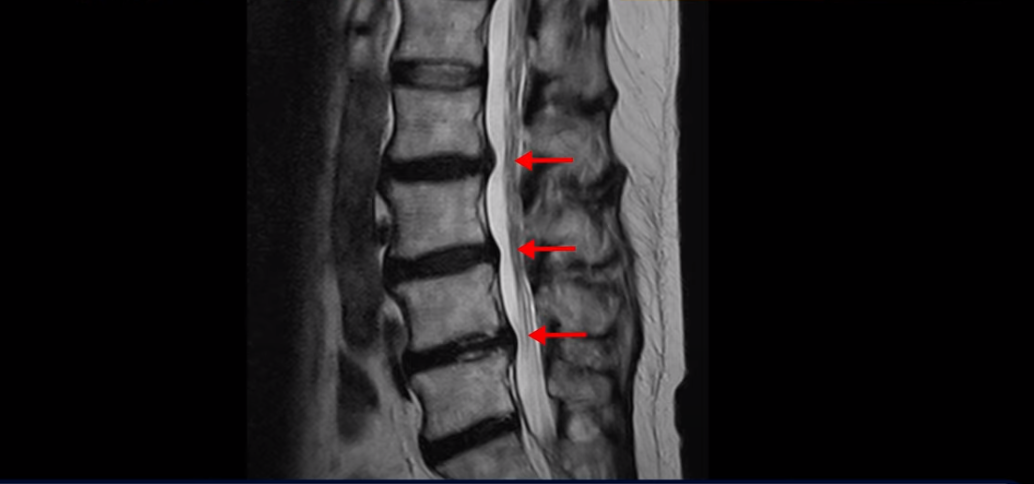

이분 MRI를 보면서 설명 드린 후 어떻게 이렇게 걷지도 못해 휠체어 타시는 환자분이 비수술 치료로 단 몇 주 만에 좋아져서 잘 걷게 될 수 있는지 또 치료는 어떻게 하는지 자세히 설명드리겠습니다.

이분 MRI를 보면 여러 마디가 퇴행이 진행되어 있고

3번 4번과 4번 5번에 중심성 협착이 있는데

4번 5번이 더 심합니다.

또 4번 5번 마디에 오른쪽으로 찢어져서 밀려나온 디스크 탈출이 보입니다.

밀려나온 수핵이 조금 흘러내려 있습니다.